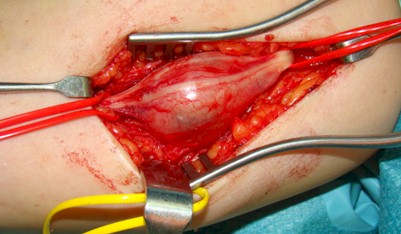

Figura 2: Exposición quirúrgica de la lesión

Bajo bloqueo del plexo braquial e isquemia se realizó una incisión cutánea en “S” alargada sobre el eje mayor del tumor, disección subcutánea y exposición de la lesión envuelta en su cápsula. Con gafas lupa y material microquirúrgico se llevó a cabo la enucleación intracapsular del tumor, tras la disección cuidadosa del resto de fascículos nerviosos no afectos (figuras 2 y 3).